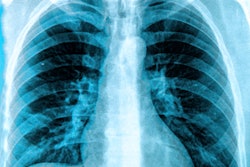

The World Health Organization (WHO) published rapid guidance on July 30 in Radiology regarding the use of chest imaging for the diagnosis and management of patients with COVID-19.

An international team of authors developed the guide over two months using online meetings and a process of rapid systematic reviews to assess the acceptability, feasibility, and impact of chest radiography, chest CT, and lung ultrasound for COVID-19 imaging.

The guide includes three recommendations for COVID-19 diagnosis:

- Chest imaging is not suggested to diagnose COVID-19 in asymptomatic patients.

- Chest imaging is not suggested to diagnose COVID-19 in symptomatic patients when reverse transcription polymerase chain reaction (RT-PCR) testing is available and timely.

- Chest imaging is suggested to diagnose COVID-19 in symptomatic patients when RT-PCR testing is not available or has delayed results, or when an initial RT-PCR test is negative but there is still high clinical suspicion of COVID-19.

The guidance also contains four recommendations for using imaging for patient management:

- Chest imaging is suggested to help clinicians decide whether to admit or discharge patients with mild COVID-19 symptoms.

- Chest imaging is suggested to help clinicians decide whether to admit patients with moderate-to-severe COVID-19 symptoms to a regular ward or to an intensive care unit.

- Chest imaging is suggested to help inform the therapeutic management of hospitalized patients with moderate-to-severe COVID-19 symptoms.

- Chest imaging is not suggested to help inform discharge decisions for hospitalized patients whose symptoms have resolved.

The authors cautioned the recommendations are conditional and based on expert opinions and low or very low certainty evidence from 28 studies. The recommendations are also for chest imaging in general -- not for specific modalities.

"While there is accumulating evidence about typical findings with each imaging modality, evidence about comparative diagnostic and prognostic value of the different modalities is still lacking," the authors wrote.